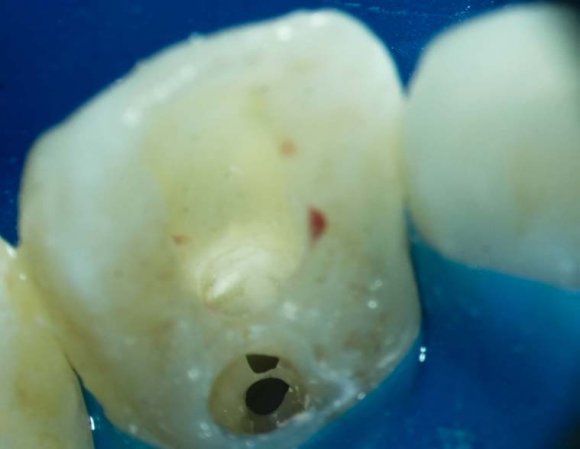

Also, there were signs in favor of internal resorption. The defect was below the cervical part, which is not typical of external cervical resorption. The response to cold stimuli reduced, which is not characteristic of external resorption, as it affects the pulp only in the last stages of tooth structures decay. Furthermore, the X-ray obliteration of the root canal beyond the resorption area is not characteristic of external resorption. Visit 1: Pre-op X-ray plus anesthesia with sol. Ubisthesini 4% -1 ml, isolation with rubberdam. The access was made as close as possible to the incisal edge. When opened, at first glance the pulp chamber looked quite II.